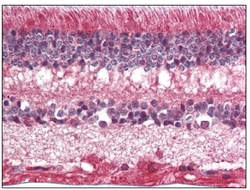

AP08544PU-N IHC

Full details

Method: